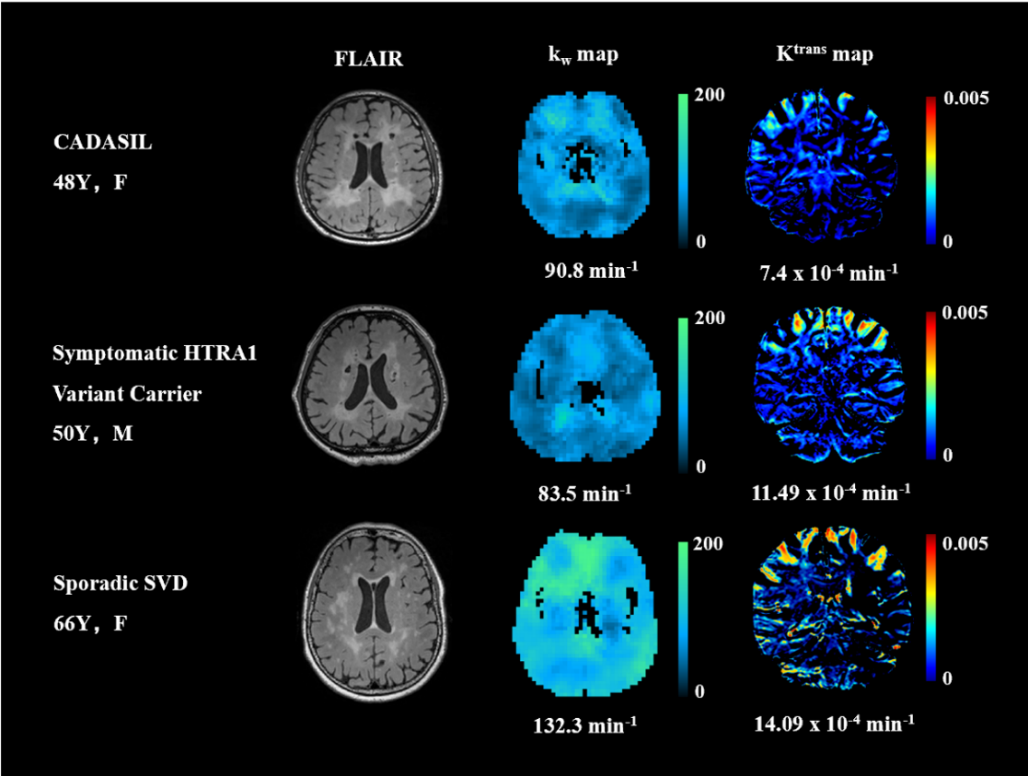

血脑屏障研究新进展!Alzheimers Dement|复旦大学程忻:合作揭示脑小血管病血脑屏障功能障碍潜在机制的异质性

2024年5月24日(当地时间),复旦大学附属华山医院神经内科程忻课题组与首都医科大学附属北京朝阳医院放射介入影像中心杨旗课题组、首都医科大学宣武医院神经内科王朝东课题组合作,于期刊Alzheimer’s & Dementia发表题为《脑小血管病血脑屏障功能障碍的异质性》(Phenotypic and Immunological Characterization of Patients with Activated PI3Kδ Syndrome 1 Presenting with Autoimmunity)的论文。该研究利用美国南加州大学王炯炯团队研发的测量血脑屏障水交换率磁共振新技术,对各脑小血管病亚型中血脑屏障功能障碍的潜在机制做出推测,为进一步理解其病理生理机制,未来开展精准治疗提供见解。